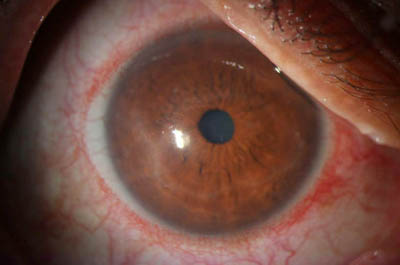

Aspecto Clínico

- Superficie corneal irregular y grisacea

- Opacidades granulares en parche

- Formación de anillo inmunológico

Superficie corneal irregular y grisácea

Opacidades granulares en parche

Opacidades superficiales satélites

Ulceración epitelial variante

Anillo inmunológico de Wessely

- Es la expresión de la interacción de los antígenos extraños con los anticuerpos que se difunden desde los vasos limbares hacia el estroma.

- Representa la formación de un complejo inmune que activa el sistema del complemento.

- El anillo de Wessely contiene principalmente neutrófilos